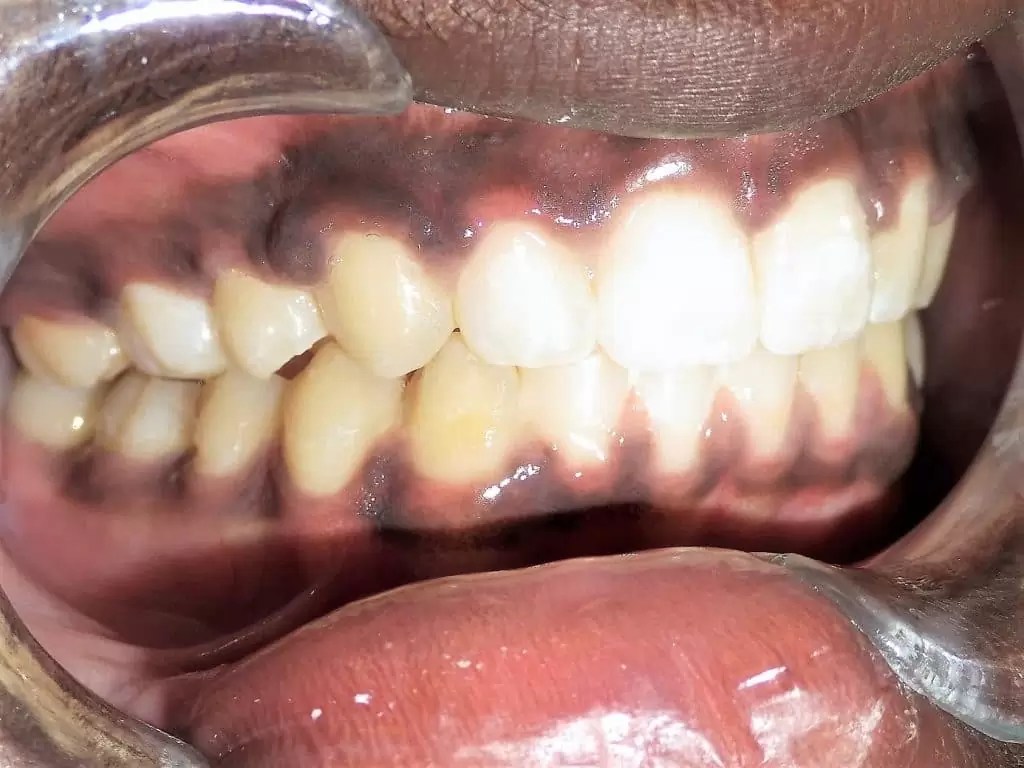

A deep dental cleaning at Miami shores orthodontist is sometimes known as scaling and planning. It is not the same as the standard cleaning you receive twice a year. You can avoid Gum disease or address it with a thorough cleaning that gets under your gums. A treatable mouth condition is gum disease and known now furthermore as periodontitis. Leaving it untreated might cause damage to the gums that cover and surround your teeth.

Your teeth and jawbone may suffer if you do not have periodontitis. In the case of gingival disease, your gums and teeth separate, leaving cracks where bacteria can flourish. Regular brushing and flossing are ineffective at eliminating these bacteria. A dental deep cleaning Miami dentist can remove harmful bacteria from your gums by deep cleaning your teeth. After that, healthy tissue can make your gums reattach to your teeth.

There's a reason your dentist is consistently reiterating the importance of teeth cleaning Miami. When bacteria grow and multiply on the teeth and gums, it forms a sticky coating called plaque. Plaque coats the teeth and creeps below the gum-line, calcifying and hardening into tartar. Tartar deposits are difficult to remove, eventually growing to separate the gums from the teeth, forming deep pockets. The tartar continues to grow and spread into these pockets, irritating and inflaming the soft gum tissue. At this point, infection sets into the periodontal tissue - an infection that can destroy gums and spread into the surrounding flesh and bone. Eventually, the infected gum tissue will lose its ability to hold onto the teeth, and the jawbone will weaken simultaneously. The result is compromised and lost teeth. Therefore, you should visit your dentist to get deep dental cleaning Miami to prevent severe gum disease.

After the examination and risk assessment are complete, a dental hygienist will perform a full professional cleaning. Even with the best brushing and flossing techniques, plaque and tartar can still find tiny crevices to hide. However, the stealthiest bacteria can't hide from good scaling and root planning. This method of deep cleaning implements a small tool that breaks down and scrapes away deposits on the teeth and below the gum line. Sometimes, a scaling tool with supersonic vibration may accelerate the process. This cleaning will keep gums healthy and improve their bond with the teeth. With a quick polish for the tooth enamel, you'll be good to go for another six months. Maintaining your bi-annual cleanings will go a long way to reducing your risk of periodontal disease.